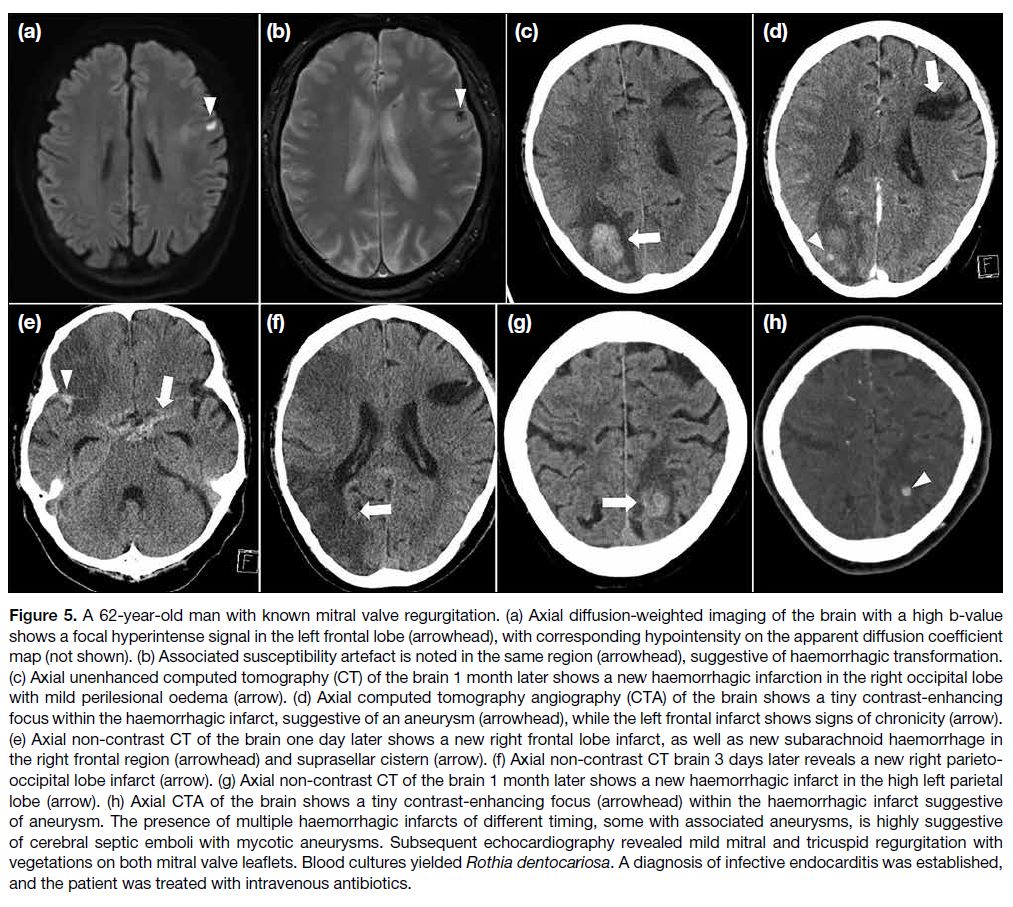

diagnosis (Figure 5).

Figure 5. A 62-year-old man with known mitral valve regurgitation. (a) Axial diffusion-weighted imaging of the brain with a high b-value

shows a focal hyperintense signal in the left frontal lobe (arrowhead), with corresponding hypointensity on the apparent diffusion coefficient

map (not shown). (b) Associated susceptibility artefact is noted in the same region (arrowhead), suggestive of haemorrhagic transformation.

(c) Axial unenhanced computed tomography (CT) of the brain 1 month later shows a new haemorrhagic infarction in the right occipital lobe

with mild perilesional oedema (arrow). (d) Axial computed tomography angiography (CTA) of the brain shows a tiny contrast-enhancing

focus within the haemorrhagic infarct, suggestive of an aneurysm (arrowhead), while the left frontal infarct shows signs of chronicity (arrow).

(e) Axial non-contrast CT of the brain one day later shows a new right frontal lobe infarct, as well as new subarachnoid haemorrhage in

the right frontal region (arrowhead) and suprasellar cistern (arrow). (f) Axial non-contrast CT brain 3 days later reveals a new right parieto-occipital

lobe infarct (arrow). (g) Axial non-contrast CT of the brain 1 month later shows a new haemorrhagic infarct in the high left parietal

lobe (arrow). (h) Axial CTA of the brain shows a tiny contrast-enhancing focus (arrowhead) within the haemorrhagic infarct suggestive

of aneurysm. The presence of multiple haemorrhagic infarcts of different timing, some with associated aneurysms, is highly suggestive

of cerebral septic emboli with mycotic aneurysms. Subsequent echocardiography revealed mild mitral and tricuspid regurgitation with

vegetations on both mitral valve leaflets. Blood cultures yielded Rothia dentocariosa. A diagnosis of infective endocarditis was established,

and the patient was treated with intravenous antibiotics.